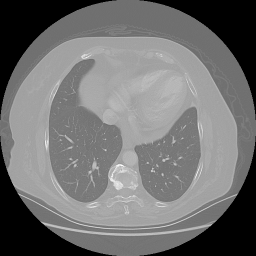

Original VENOUS CT scan

No window - Raw intensity values

Lung window (WL -600, WW 1500 β†’ Low βˆ’1350, High +150)